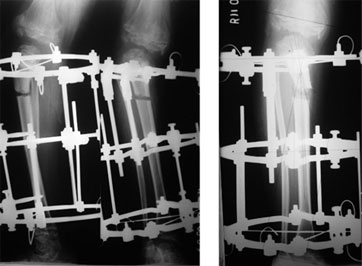

The deformity in the proximal tibia was corrected using the gradual correction using Ilizarov ring fixator and hinges.

The fixator is first applied in a crooked fashion, to mimic the deformity of the bone. With gradual distraction @ 1 mm/day the fixator is adjusted and the bone moves with the fixator creating a gap at the osteotomy site(the bone cut).

The gap shown in the xray is the site of osteotomy & correction of the deformity.

The picture on the right side shows correction achieved in terms of the angle and length. The fuzzy appearance in the bone gap is due to the formation of new bone in the gap. |